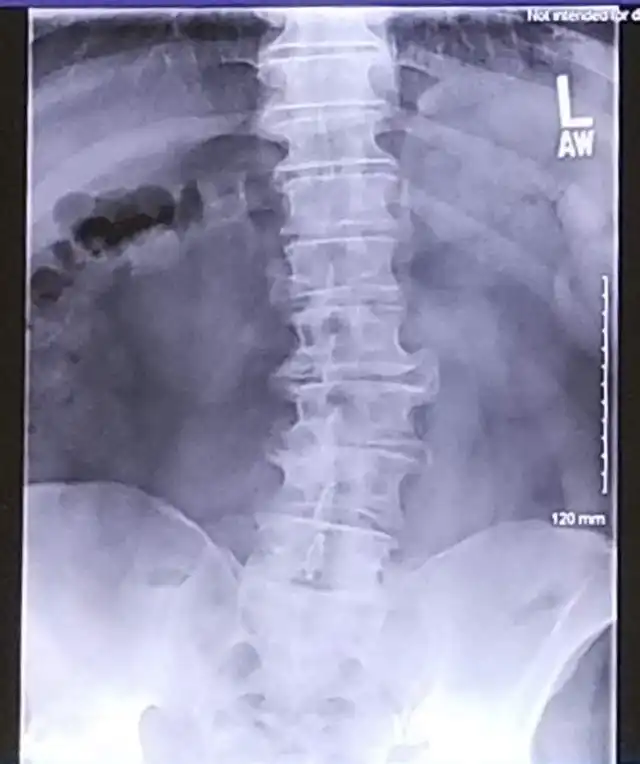

"Скинул рентген жене, надеясь на сочувствие. Она сказала, что мой позвоночник похож на проселочную дорогу"